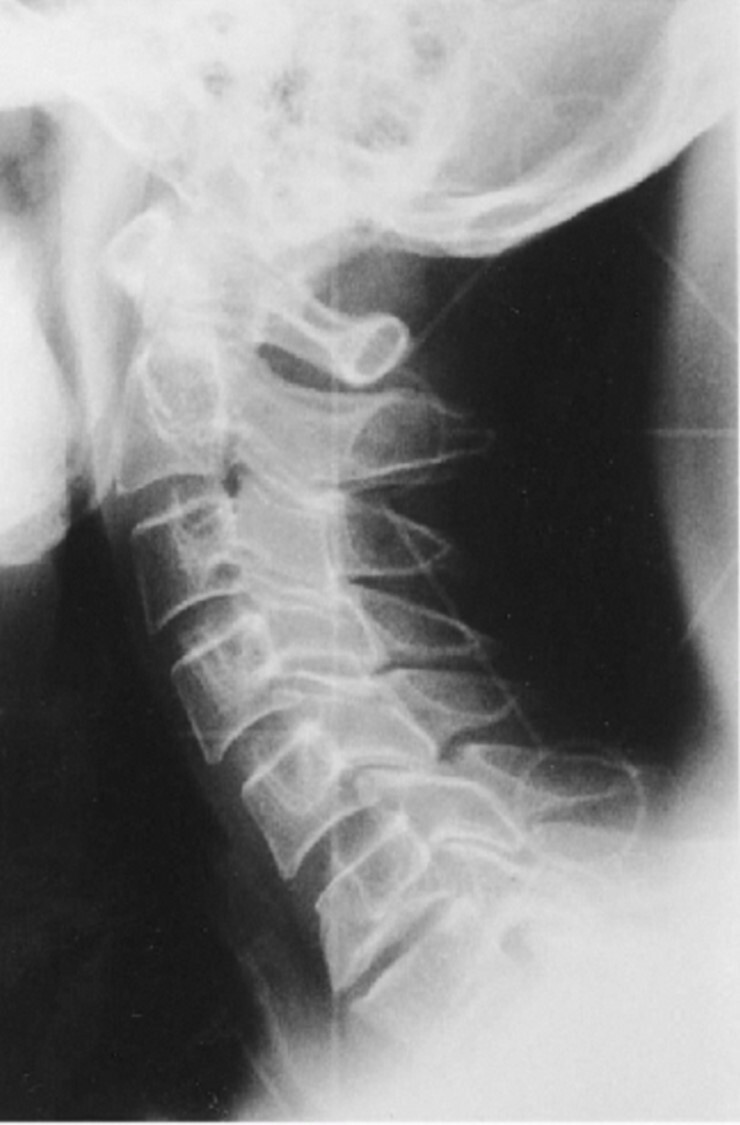

10

Q

What is the cause of the artifact seen in the

attached image?

A

Upside-down focused grid resulting in grid cut-off